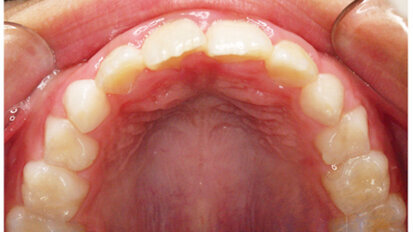

Rendre des facettes unitaires si naturelles qu'elles soient indétectables

Comme les patients vieillissent, les dents antérieures présentent souvent de l'usure, de l'effritement et de la décoloration. Ces ...